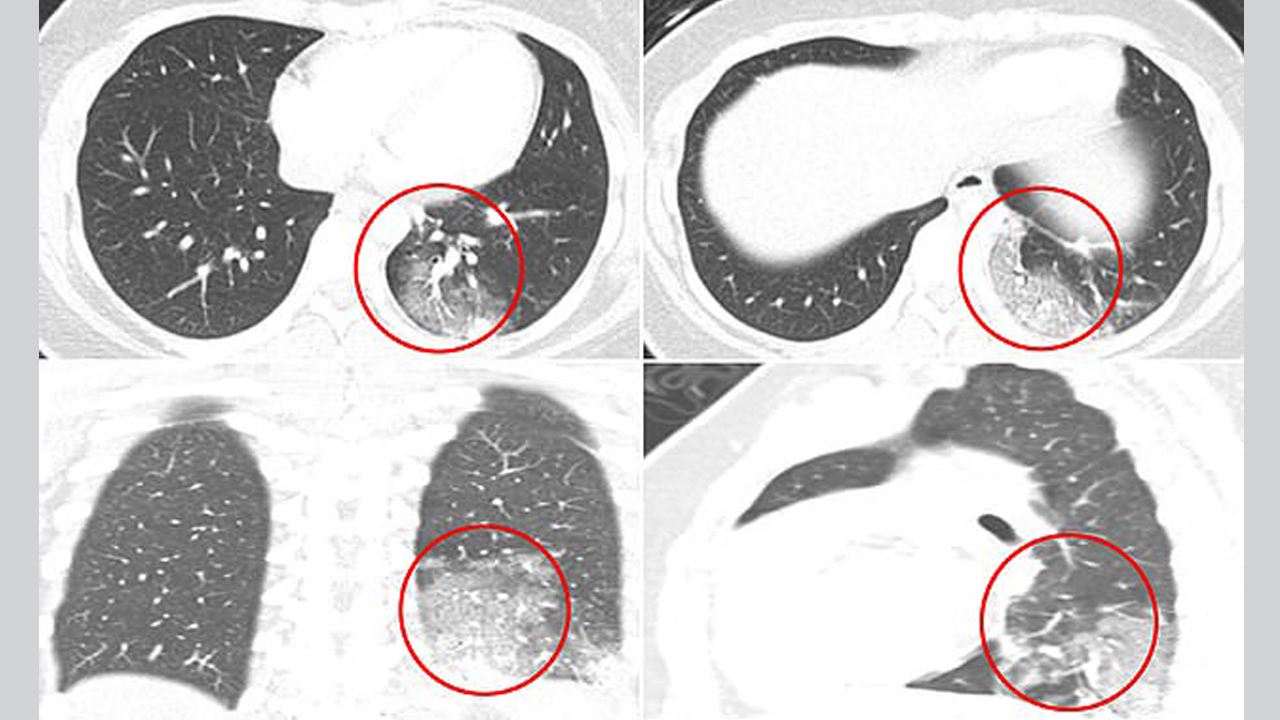

بالصور.. هكذا تبدو رئة الأطفال المصابين بـ "كوفيد-19"

نشر أطباء صوراً بالأشعة المقطعية لرئات أطفال بعد إصابتهم بالفيروس التاجي، وأظهرت الصور تلفاً في الرئة لدى المصابين، وفقاً لما جاء في موقع "ديلي ميل" البريطاني.

وقام فريق مستشفى بوسطن للأطفال بتقييم التصوير المقطعي لحالات الأطفال المصابين بـ"كوفيد-19" لمعرفة العلامات الأكثر شيوعاً.

وفي إحدى الدراسات التي أجريت على 20 طفلاً، كان ما يقرب من ثلثيهم يعانون عتامة الجدار الأرضي للرئة، وهو مؤشر إلى انتشار الالتهاب.

وعانى نصف المرضى لديهم ما يعرف بـ"علامة الهالة"، وذلك عندما يحيط الالتهاب بكتلة الرئة، وهو ما يجعل من الصعب التنفس لأن الأكياس الهوائية في الرئتين تمتلئ بمواد مثل السوائل أو العدوى.